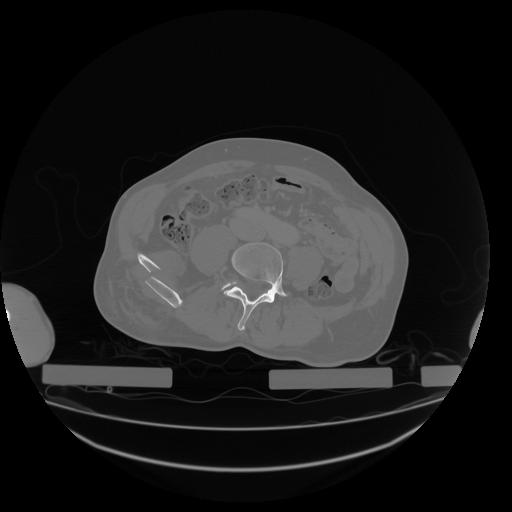

34 CUERPO,CE,Vol,1.0,CUERPO,,